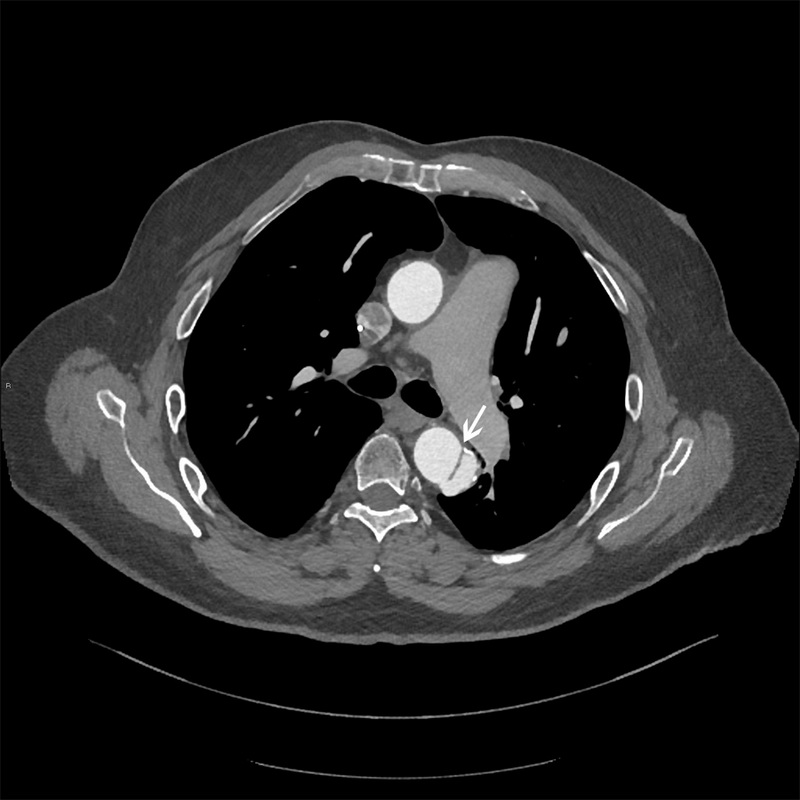

При подозрении на данное заболевание необходимо срочная и точная оценка состояния больного. Основными методами диагностики расслоения аорты являются: рентгенография грудной клетки, ЭхоКГ, УЗДГ, КТ, МРТ, аортография.